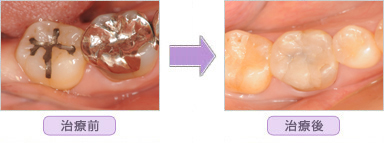

ハイブリットセラミックインレーの治療紹介

■ 右下臼歯部1本セラミック T.S様 27歳 女性

■ 右下臼歯部2本セラミック H.O様 35歳 女性

■ 右下臼歯部3本セラミック S.M様 36歳 女性

■ 左上臼歯部2本セラミック A.K様 36歳 女性